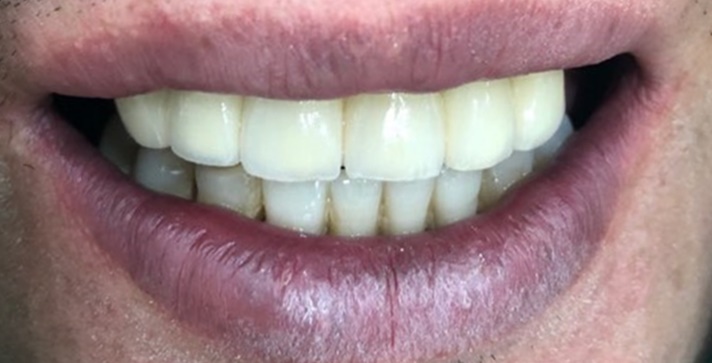

사고 직후 빠진 치아 (왼쪽 사진) -> 윗니 브릿지 및 아랫니 브릿지(오른쪽 사진)

환자분은 넘어졌다고 하셨나? 그랬지만 주변의 증언을 들으면 싸운 것 같다는...

이 환자분은 이미 치아도 빠지고 흔들리는 김에 치아 완전 고르게 해달라고 하셔서

흔들리는 이는 빠지고 치료해야 하는 치아는 처리해서 브릿지를 만들어 드렸고

환자분이 고르고 하얗게 된 이에 굉장히 만족 하셨습니다.